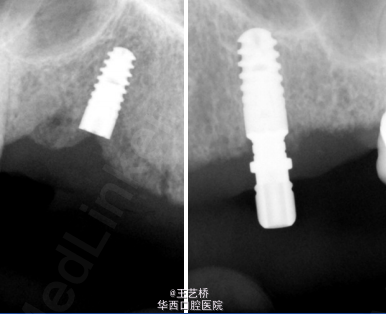

检查:16、14、13、12、11、21、22、23、24、25、27牙缺失;26牙烤瓷冠修复,边缘不密合;33-38牙可见烤瓷冠修复;45、46牙为种植修复。

诊断:牙列缺损 影像显示13、23牙槽骨质条件较好,可行种植手术,故制定种植体支持式可摘局部义齿。